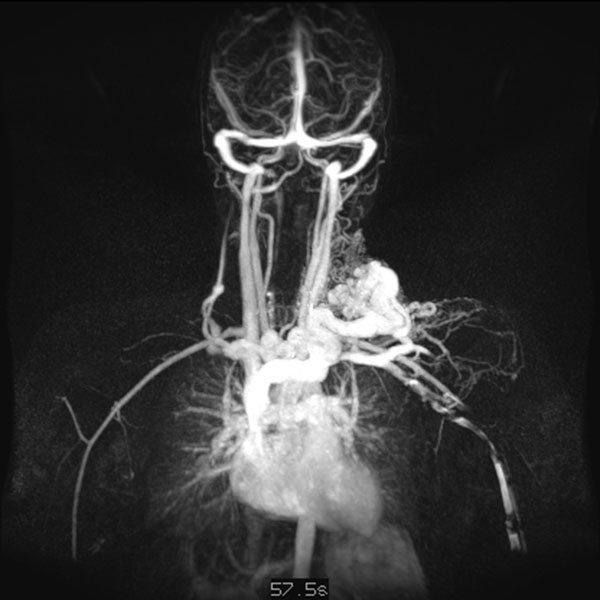

Dynamische, kontrastmittelunterstützte, zeitlich hochaufgelöste MR-Angiographie; Darstellung 57 s nach intravenöser Kontrastmittelapplikation. Weitere 5 s später nochmals bessere Darstellung des venösen Abstroms aus der arteriovenösen Malformation.